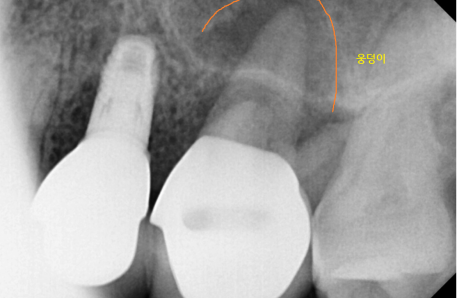

23.11.14

웅덩이가 진 것처럼 경계가 보이기도합니다.